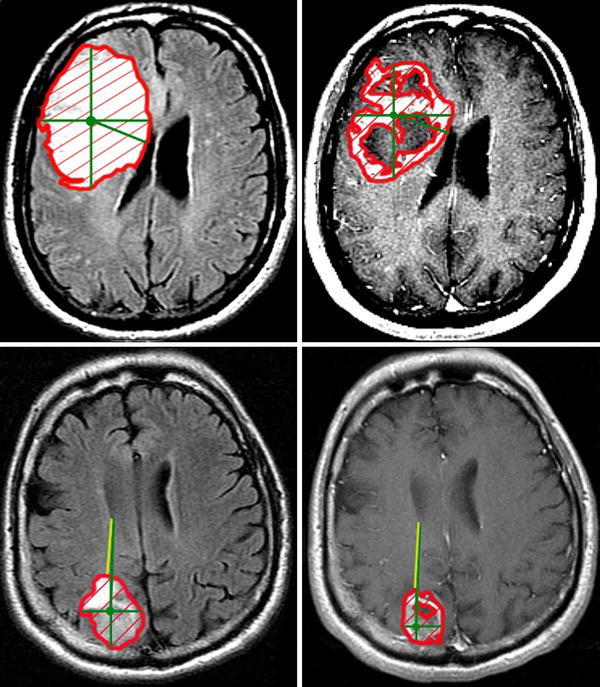

GdED and T2ED (edge distances): Distance from the edge of the abnormality to the ependyma of the ventricles was measured on GdT1WI (GdED) and T2WI images (T2ED) (Fig. 1). If the abnormality extended to the ependymal surface of the ventricle, this was noted as GdED = 0 or T2ED = 0.

Fig. 1.

Measurement of T2 volume (T2 V; left upper frame—thick red border), enhancing volume (GdV; right upper frame—thick red border), T2 edge distance (T2ED; left lower frame—radial yellow line from tumor edge to ventricle), enhancing edge distance (GdED; right lower frame—radial yellow line from tumor edge to ventricle), T2 center distance (T2CD; left upper and lower frames—green line from centroid to ventricle), and enhancing center distance (GdCD; right upper and lower frames—left upper and lower frames—green line from centroid to ventricle) for patients with T2ED = 0 and GdED = 0 (upper) and T2ED > 0 and GdED > 0. (Color figure online)

GdCD and T2CD (center distances): Distance from the geometric center of abnormality to the ventricle was measured on GdT1WI (GdCD) or T2WI (T2CD). The geometric center was defined as the intersection of the largest in-plane anteroposterior and orthogonal diameters of contrast enhancement or T2 prolongation on the axial sections demonstrating the largest area of abnormality on GdT1WI or T2WI respectively (Fig. 1).